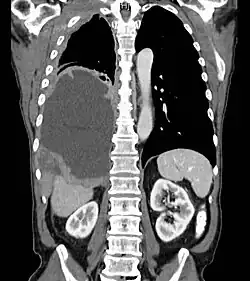

Mesothelioma Overview

- Pleural Involvement

Resectable disease

- Surgical resection possible in minority of patients

- Trimodality therapy is treatment of choice for non-metastatic mesothelioma

- Extrapleural pneumonectomy is surgical procedure of choice: Removes ipsilateral lung, parietal pleura, pericardium, diaphragm and mediastinal nodal dissection with reconstruction of the diaphragm.